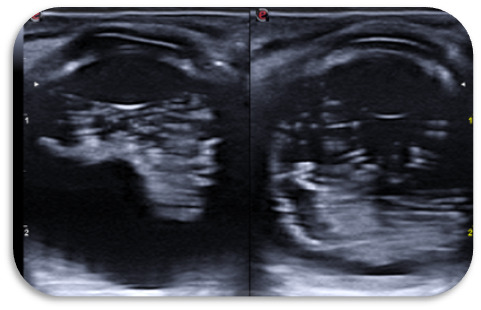

Primer caso: imagen hiperecoica avascular sin sombra posterior que ocupa todo el polo posterior, que se mueve con los movimientos oculares. La retina plegada. Ante sospecha de tumor se hace ecografía en ojo contralateral y se obtienen las mismas imágenes.

Fondo de ojo (FO) caso 1: OD: Hialosis asteroidea. Papila y mácula normal. Retina aplicada 360º. OI: Hialosis asteroide muy densa. DVP prepapilar no traccional. No vitritis. Retina aplicada.